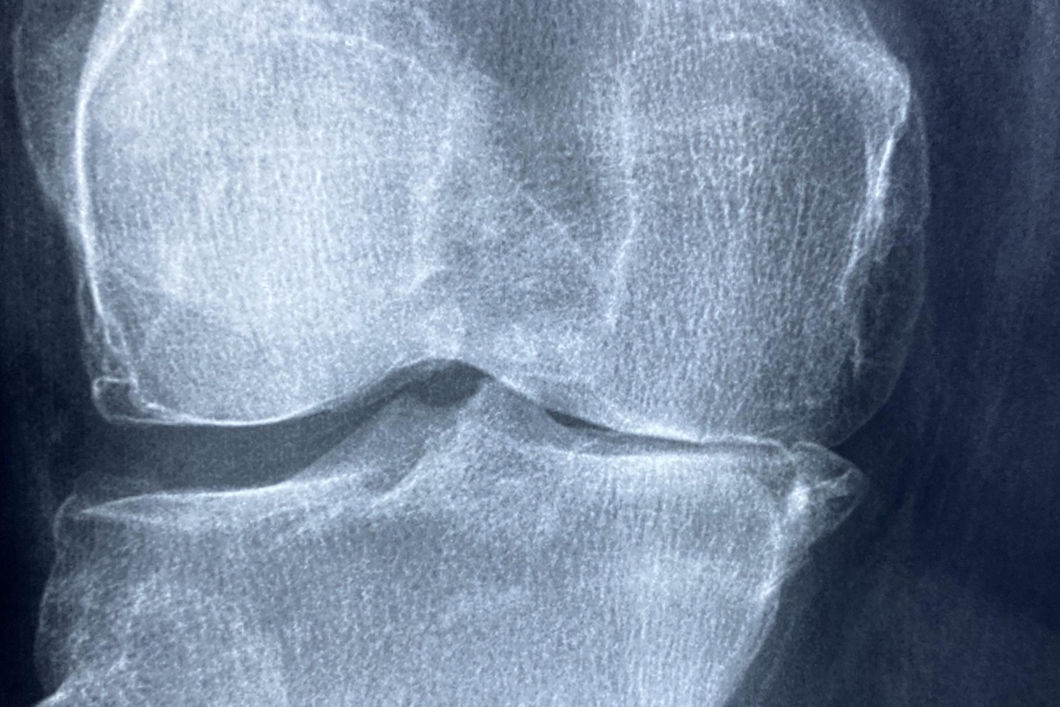

Bucky